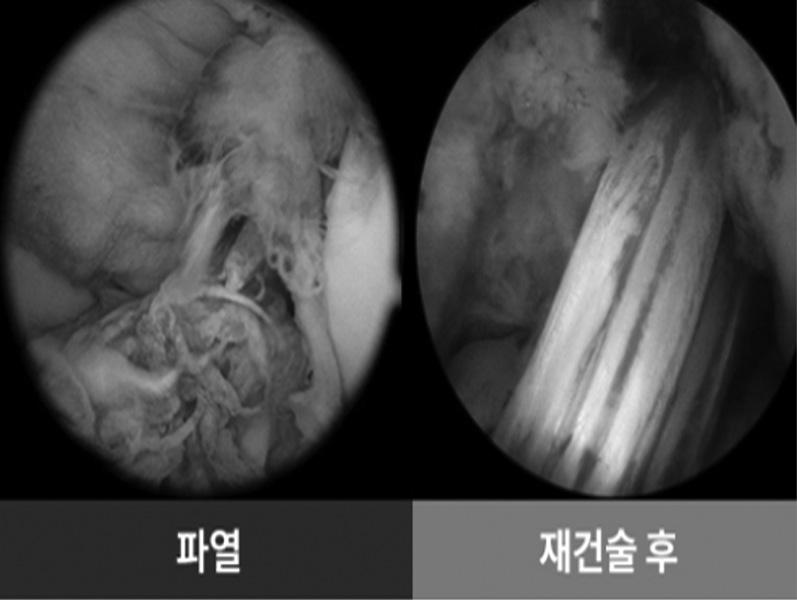

코로나19로 인한 마스크 착용 의무도 병원 을 제외하고는 전면 해지되며 야외활동이 많 이 늘고 있다. 그간 미뤘던 운동이나 스포츠 활동에 나서는 사람이 늘고 있는데 이 때 준 비 운동을 충분히 하지 않고 바로 몸을 움직 일 경우 다치기 쉽기 때문에 주의가 필요하다. 특히 축구, 농구, 테니스 등 스포츠에서 가장 쉽게 발생하는 부상이 무릎 부상으로, 그 중 대표적인 질환이 바로 십자인대파열이다.

이번 주 휴람 의료정보에서는 휴람 의료네 트워크 신세계서울병원 서보경 병원장의 도 움을 받아 십자인대파열에 대해 자세히 알아

보고자 한다.

십자인대는 무릎에 위치한 십자모양으로

교차되어 있는 전방, 후방 2개 인대를 일컬으

며 무릎을 움직이게 하고 관절이 앞뒤로 이

탈되는 것을 방지하는 역할을 한다. 그런데

갑작스런 방향전환이나 외부의 충격, 점프 후

착지 시 충격이 가해지면 십자인대가 파열될 수 있다. 스포츠 선수들뿐만 아니라 활동적 인 운동을 즐겨하는 일반인들 사이에서도 해 당 부상이 점점 증가하고 있다.

십자인대파열의 주된 증상은 극심한 무 릎통증이다. 인대 파열 시 무릎에서 ‘뚝’하는

파열음을 들을 수도 있고, 이후 부기와 열감

을 동반하며 무릎관절이 흔들리거나 불안정

한 느낌을 받기도 한다. 부분파열의 경우 무

릎 통증 정도만 호소해 심각성을 깨닫지 못

한 채 방치하는 경우도 많다.

환자에 따라 통증의 강도가 다를 수는 있

지만, 일단 한 번 손상된 인대는 자연적으로

치유되기가 어렵다. 또한 파열을 방치할 경우

관절 사이 연골판의 손상이나 퇴행성관절염

등 2차 질환으로 이어질 수도 있으므로 늦지

않게 병원을 찾아 제대로 된 진단과 치료를

받는 것이 바람직하다.

십자인대파열 치료는 정도가 심하지 않은

경우 비수술적 치료가 시행된다. 목발이나 보

조기를 이용하여 손상된 십자인대를 보조하

며 약물치료 및 물리치료 등을 병행하여 통

증을 완화시킬 수 있다. 또한 관절 가동범위

훈련 및 근력강화 운동을 시행하여 무릎의

기능도 회복시키게 된다.

그러나 파열정도가 심각한 경우 수술적

치료가 필요하다. 수술적 치료의 경우 관절내

시경을 이용하여 다른 인대를 이식해주는 십 자인대 재건술을 시행한다. 경골 및 대퇴골에

십자인대가 붙는 위치를 타겟으로 하여 뼈

터널을 생성한 뒤, 새로운 인대를 넣어 금속

등을 이용해 뼈에 고정해주는 방법이다.

관절내시경을 통해 시행되는 ‘십자인대재 건술’은 관절의 절개 부위가 1cm미만으로 매 우 작고 출혈, 흉터도 거의 없으며 수술시간 과 입원기간도 짧은 편으로 환자의 부담이 적은 장점이 있다. 또한 특수 소형 카메라가 달려있는 관절내시경을 병변 부위에 삽입하 여 송출되는 화면을 직접 보면서 치료하기 때 문에 더 정확하고 안전한 치료방법이다. 휴람 의료네트워크 신세계서울병원 서보 경 병원장은 “무엇보다 중요한 것은 십자인 대파열이 발생하지 않도록 주의하는 것이며, 수술 후 관리도 매우 중요하다. 수술 후 일상 생활은 3개월 정도면 충분히 회복되지만 스 포츠 활동 등 손상 전과 같은 정도로의 회복 은 6개월 이상이 소요되므로 그 때까지 무릎 관절을 무리하게 사용하는 것은 절대 금물 이다”라며 “특히 무릎을 꿇거나 쪼그려 앉는 등, 무릎에 압박을 가하는 행동은 최대한 자 제하는 것이 좋다. 또한 무릎관절의 운동 범 위를 서서히 늘려주는 재활운동을 꾸준히 하 는 것이 빠른 회복을 위해 가장 중요하다”고 전했다.